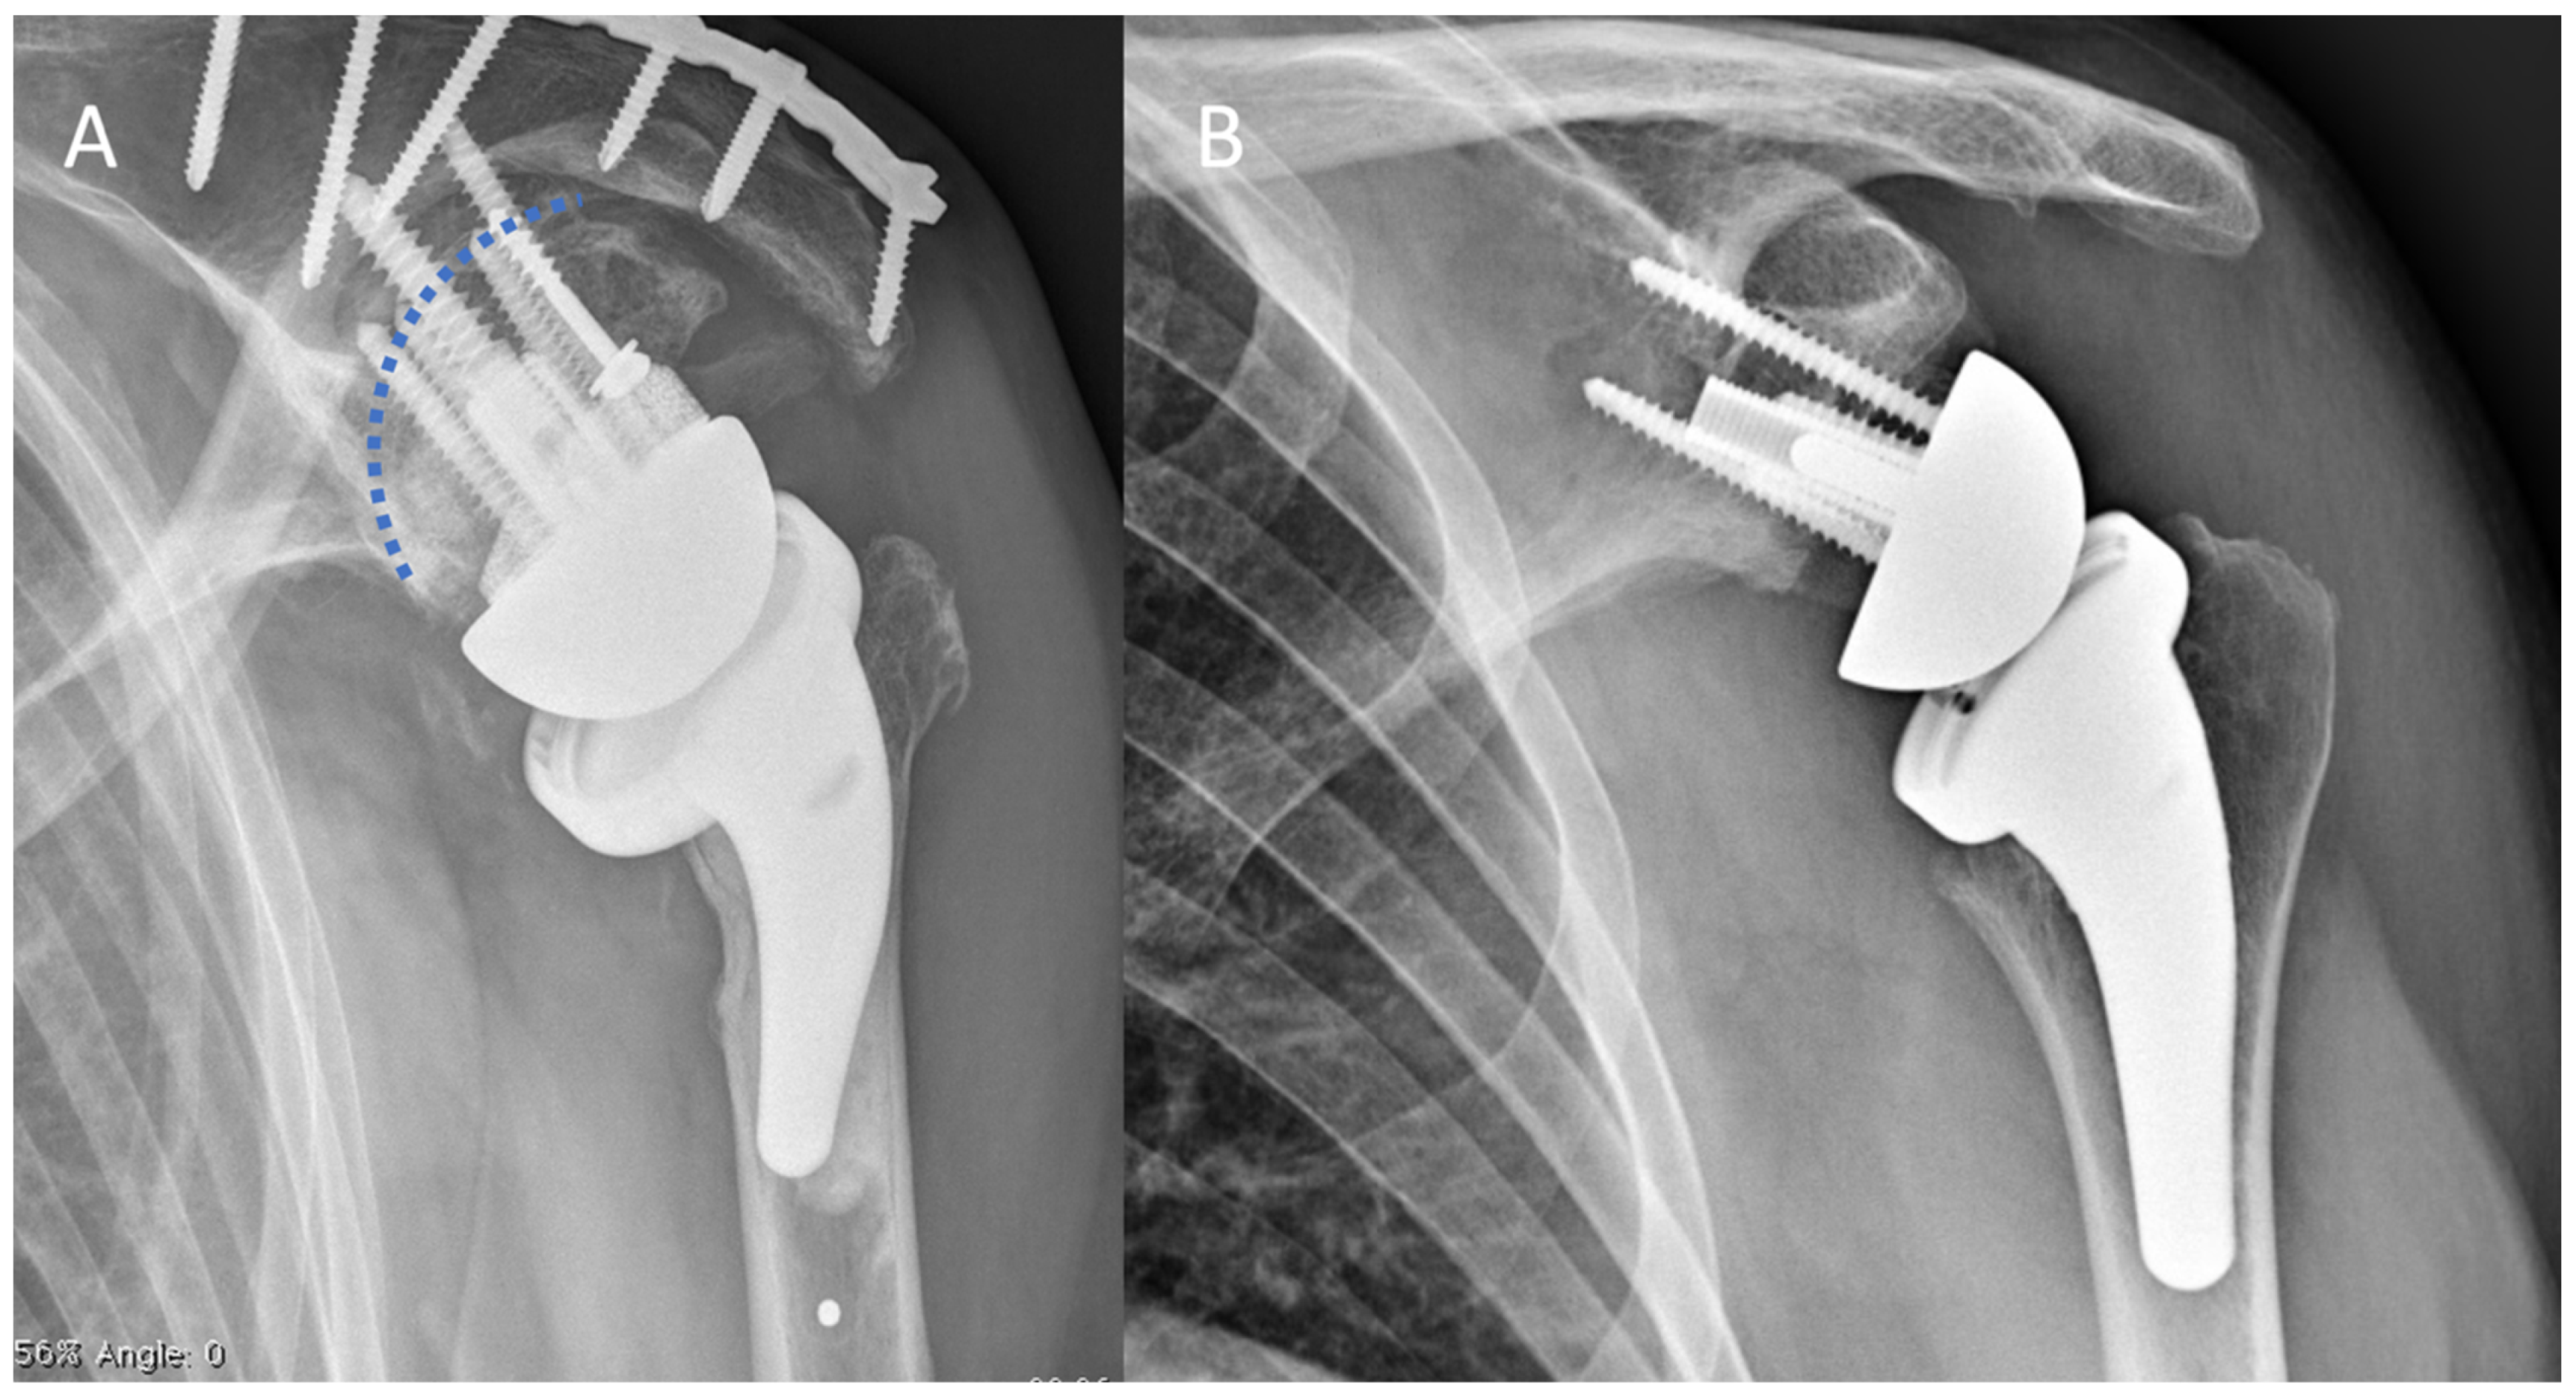

2.2. Surgical Technique and Implant Design